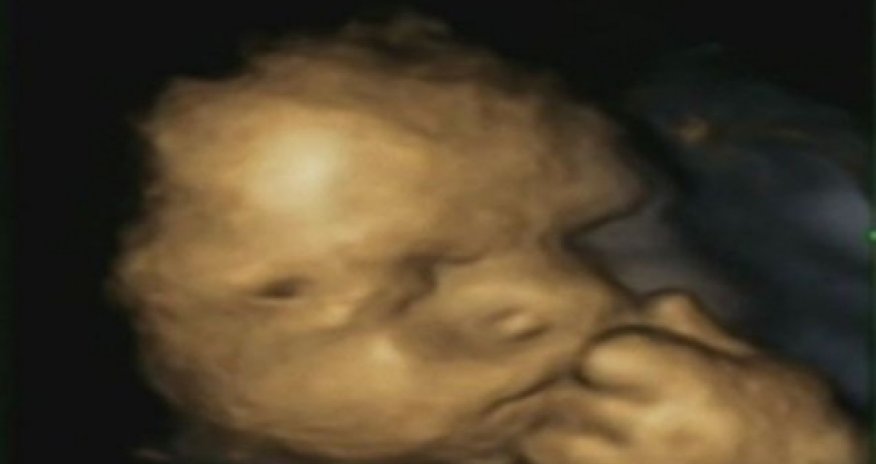

Is this picture proof that unborn babies feel mother's stress?

But the tiny hand pulled up to the chin reveals that, upsettingly, this baby appears to be under stress.The remarkable image was taken as part of a study showing unborn children touch their faces more often if their mother has been anxious, helpless or under pressure.Researchers believe they are picking up on her anxieties – and then trying to soothe them away with the power of touch. As adults, we do this by holding our head in our hands. But while we use both hands, babies of stressed-out mothers preferred the  touch of just one.Although previous studies have found babies pick up on stress in the womb, this is believed to be the first to offer  photographic evidence.Researcher Nadja Reissland from Durham University gave 15 mothers-to-be 4D ultrasound scans four times during their pregnancy.Rather than the grainy, ‘flat’ images produced by the 2D scanners usually used by the NHS, a 4D machine stitches together pictures taken from a variety of angles to create clear three-dimensional pictures.These are then recorded on video – the fourth dimension.The mothers-to-be were quizzed on their  levels of stress in the month leading up to each scan and the videos were analysed to see how often the unborn babies touched their faces. In total, the eight girls and seven boys did so 342 times.The more anxious the woman was, the more the unborn child mopped its brow, the journal Laterality: Asymmetries of Body, Brain and Cognition reported. Dr Reissland believes that the babies were picking up on an increase in the stress hormone cortisol being  produced by their mothers.The study also found those whose mothers had been under pressure were more likely to use their left hand when touching their face.This is significant because attention deficit hyperactivity disorder, autism, depression and schizophrenia all more common in people who are left-handed.Dr Reissland said: ‘Most mothers are fine and needn’t worry but some will need to think about reducing their stress.’(dailymail.co.uk)Bakudaily.az